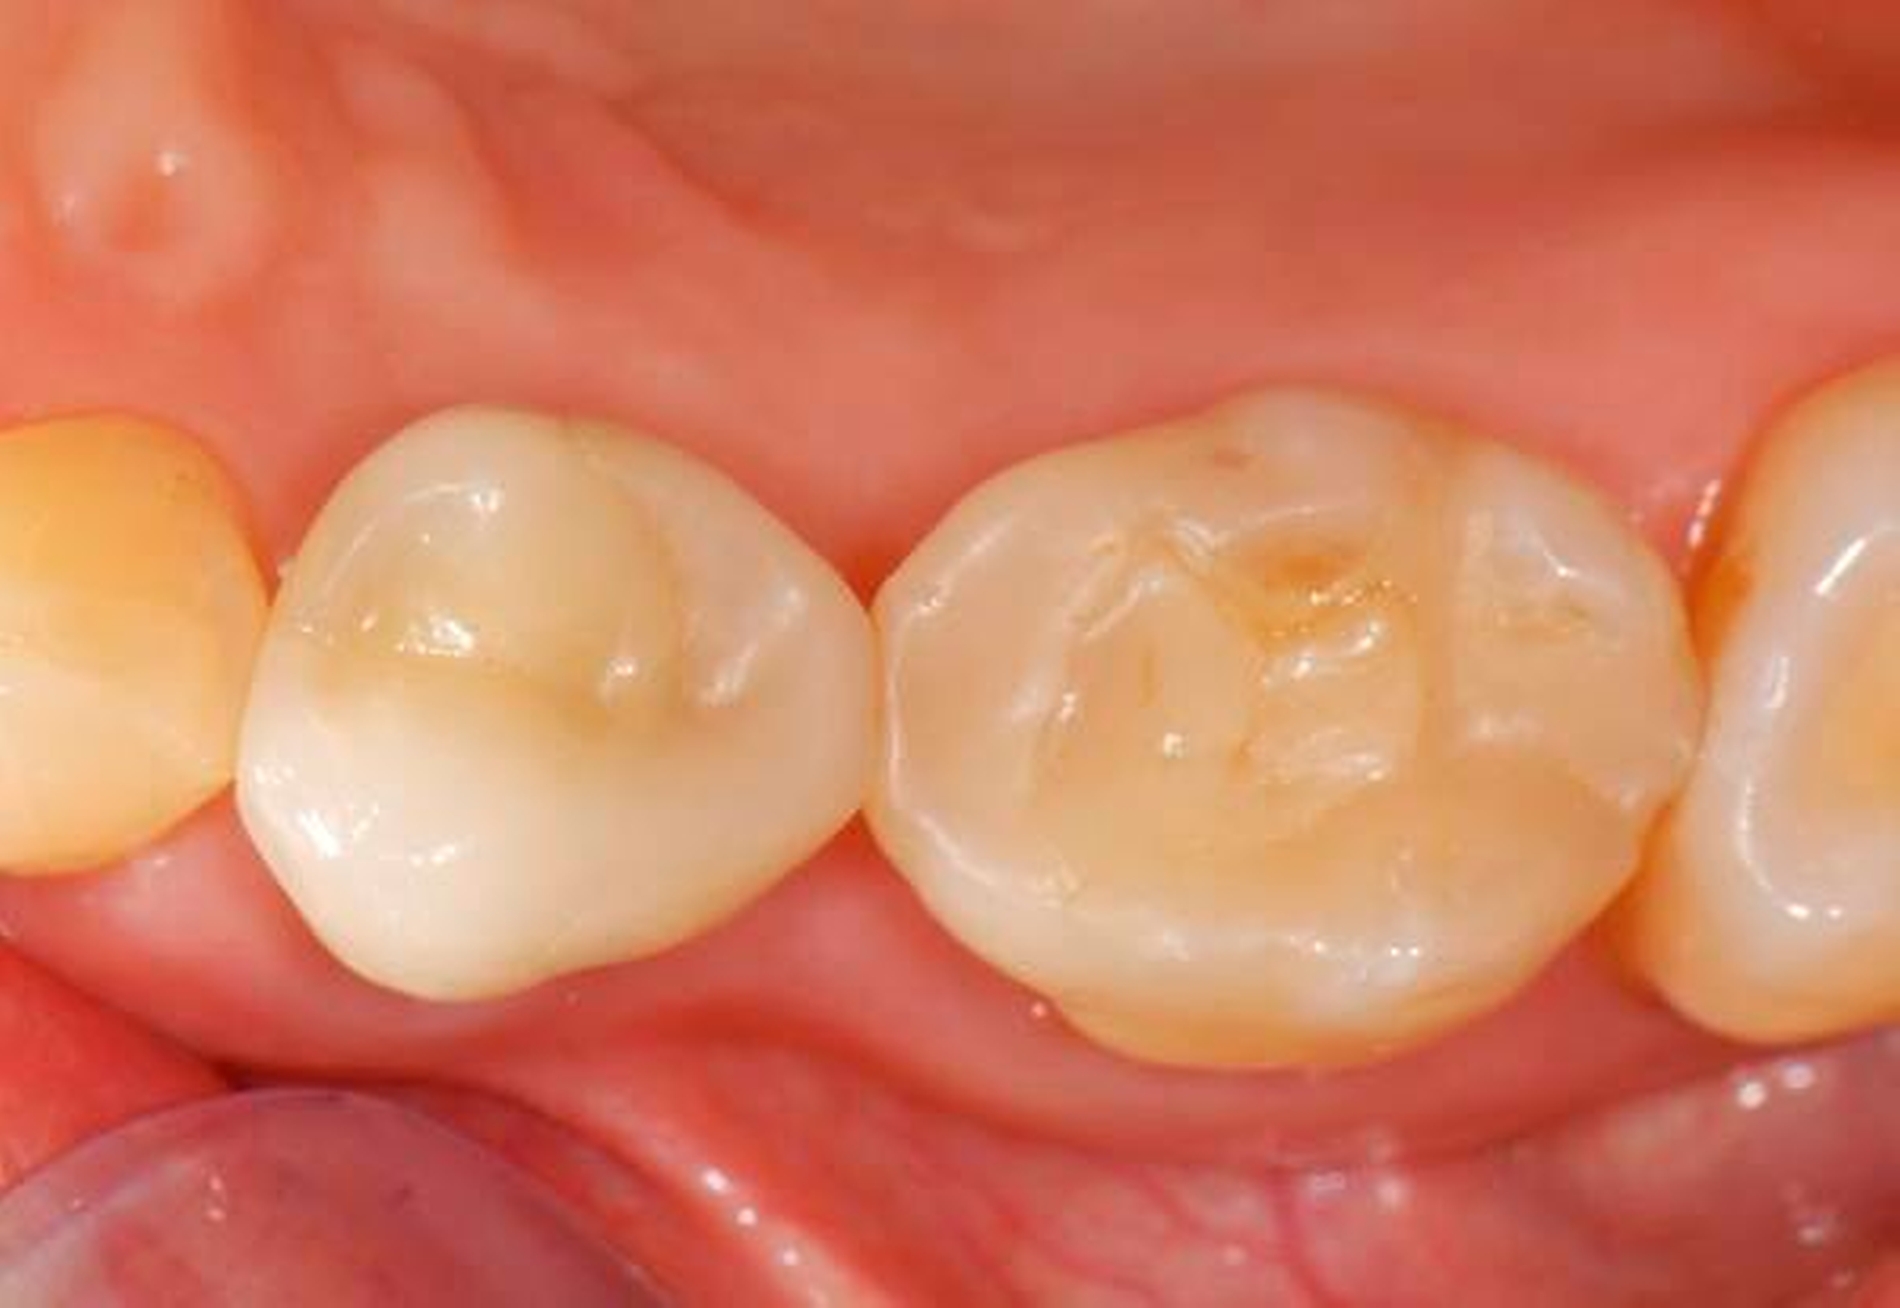

Abbildung 2: Direkte Teilüberkronung im Seitenzahnbereich (R1-Technik)

In den Abbildungen 1 bis 3 werden Optionen für frugale Interventionen auf restaurativem Sektor aufgeführt. Es handelt sich um direkte Vollüberkronungen im Frontzahnbereich (hier: hergestellt in R1-Technik / einphasig) (Abbildung 1), direkte Teilüberkronungen im Seitenzahnbereich (hier: hergestellt in R1-Technik / einphasig) (Abbildung 2), Reparatur-Restaurationen im Seitenzahnbereich (hier: hergestellt in R2-Technik / zweiphasig) (Abbildung 3). Technische Einzelheiten zur Vorgehensweise und den Ergebnissen sind an anderer Stelle beschrieben (Literatur siehe oben).

Für die in Abbildung 2 dargestellte Situation eines tief zerstörten Prämolaren gelten ähnliche Charakteristika. Es gibt in der restaurativen Zahnheilkunde viele Neuerungen, die das Behandlungsspektrum vergrößert haben. Dazu zählen unter anderem:

ein- oder zweiphasiges Vorgehen je nach Defektausdehnungen (R1- und R2-Technik),

von Präparationsgrenzen unabhängige Verschalungstechniken, die auch bei nicht-kariesbedingten Zahnhartsubstanzschäden (wie etwa Hypomineralisationen) zum Einsatz kommen können,

schadensgerechte Reparaturtechniken (Abbildung 3),

neuartige Insertionstechniken, die unter anderem die Anpassung neuer Restaurationen an vorhandene prothetische Versorgungen (Reziproktechnik) erlauben.